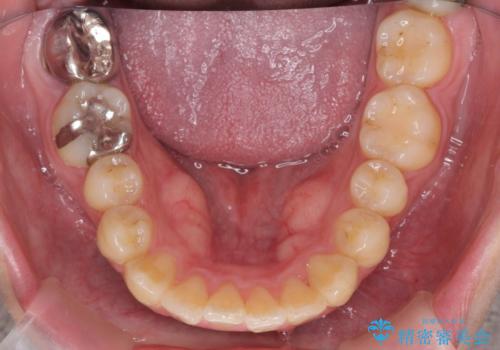

歯を抜かずに行う前歯の角度の改善

- 歯を抜かずに前歯の角度を改善したい、と矯正治療を希望され来院されました。

可及的に前歯部にIPR(歯間の削合)を行い、抜歯をせずマウスピース矯正システムインビザラインで歯の排列を行っていく治療計画としました。

治療の前後を比べると、がたつきや歯の角度が改善したことがしっかりと確認されました。